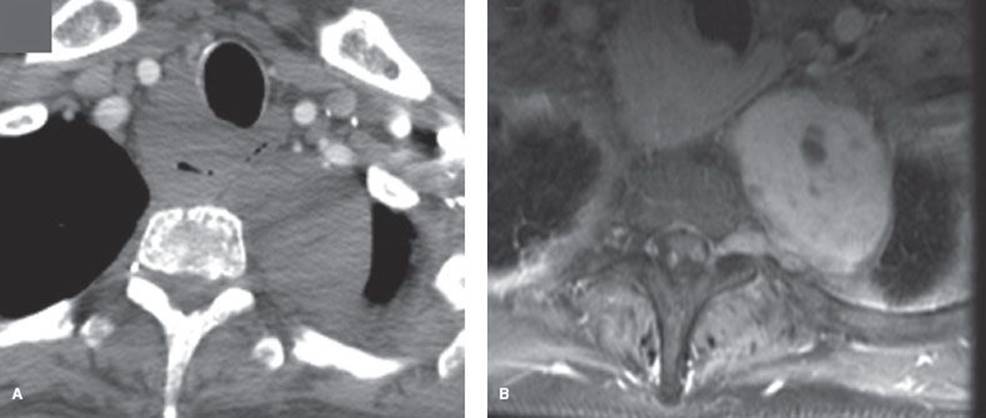

Figure 29.3 Benign and malignant neurogenic tumors. A: Benign neurogenic tumor with bony erosion, widening of the foramen, and extension into the spinal canal. None of these signs are associated with malignancy. B: Ganglioneuroblastoma in an adult. The large size is associated with a likelihood of malignancy.

A study of CT imaging of posterior neurogenic tumors in 68 adults identified four imaging features that were associated with malignancy: (a) Size >10 cm (malignancy in almost all patients), (b) bone destruction (four out of four patients), (c) pleural effusion (two out of two patients), and (d) mediastinal displacement (one out of two patients).2 However, while bone destruction was strongly predictive of malignancy, some degree of bony abnormality was noted in 32% (22/68); these findings include erosions, splaying of the ribs, foraminal enlargement, or localized scoliosis and were not associated with malignancy (Fig. 29.3A,B).2

MRI is an accurate test to assess for a dumbbell tumor.21 Because CT may miss an intraspinal component,20 MRI is indicated whenever the tumor is contiguous with a neural foramen, there is a widened intervertebral foramen or erosion of a vertebral body or pedicle (Fig. 29.4A,B).21 MRI is more sensitive than traditional myelography.20 In addition, magnetic resonance angiography (MRA) can be useful in lower posterior mediastinal tumors to locate the artery of Adamkiewicz instead of arteriography, which has a 2% complication rate.20

Figure 29.4 Schwannoma in a woman with neurofibromatosis. A: CT with IV contrast does not clearly show invasion through the foramen. B: MRI (T1 postcontrast) image shows invasion through the foramen into the spinal canal.